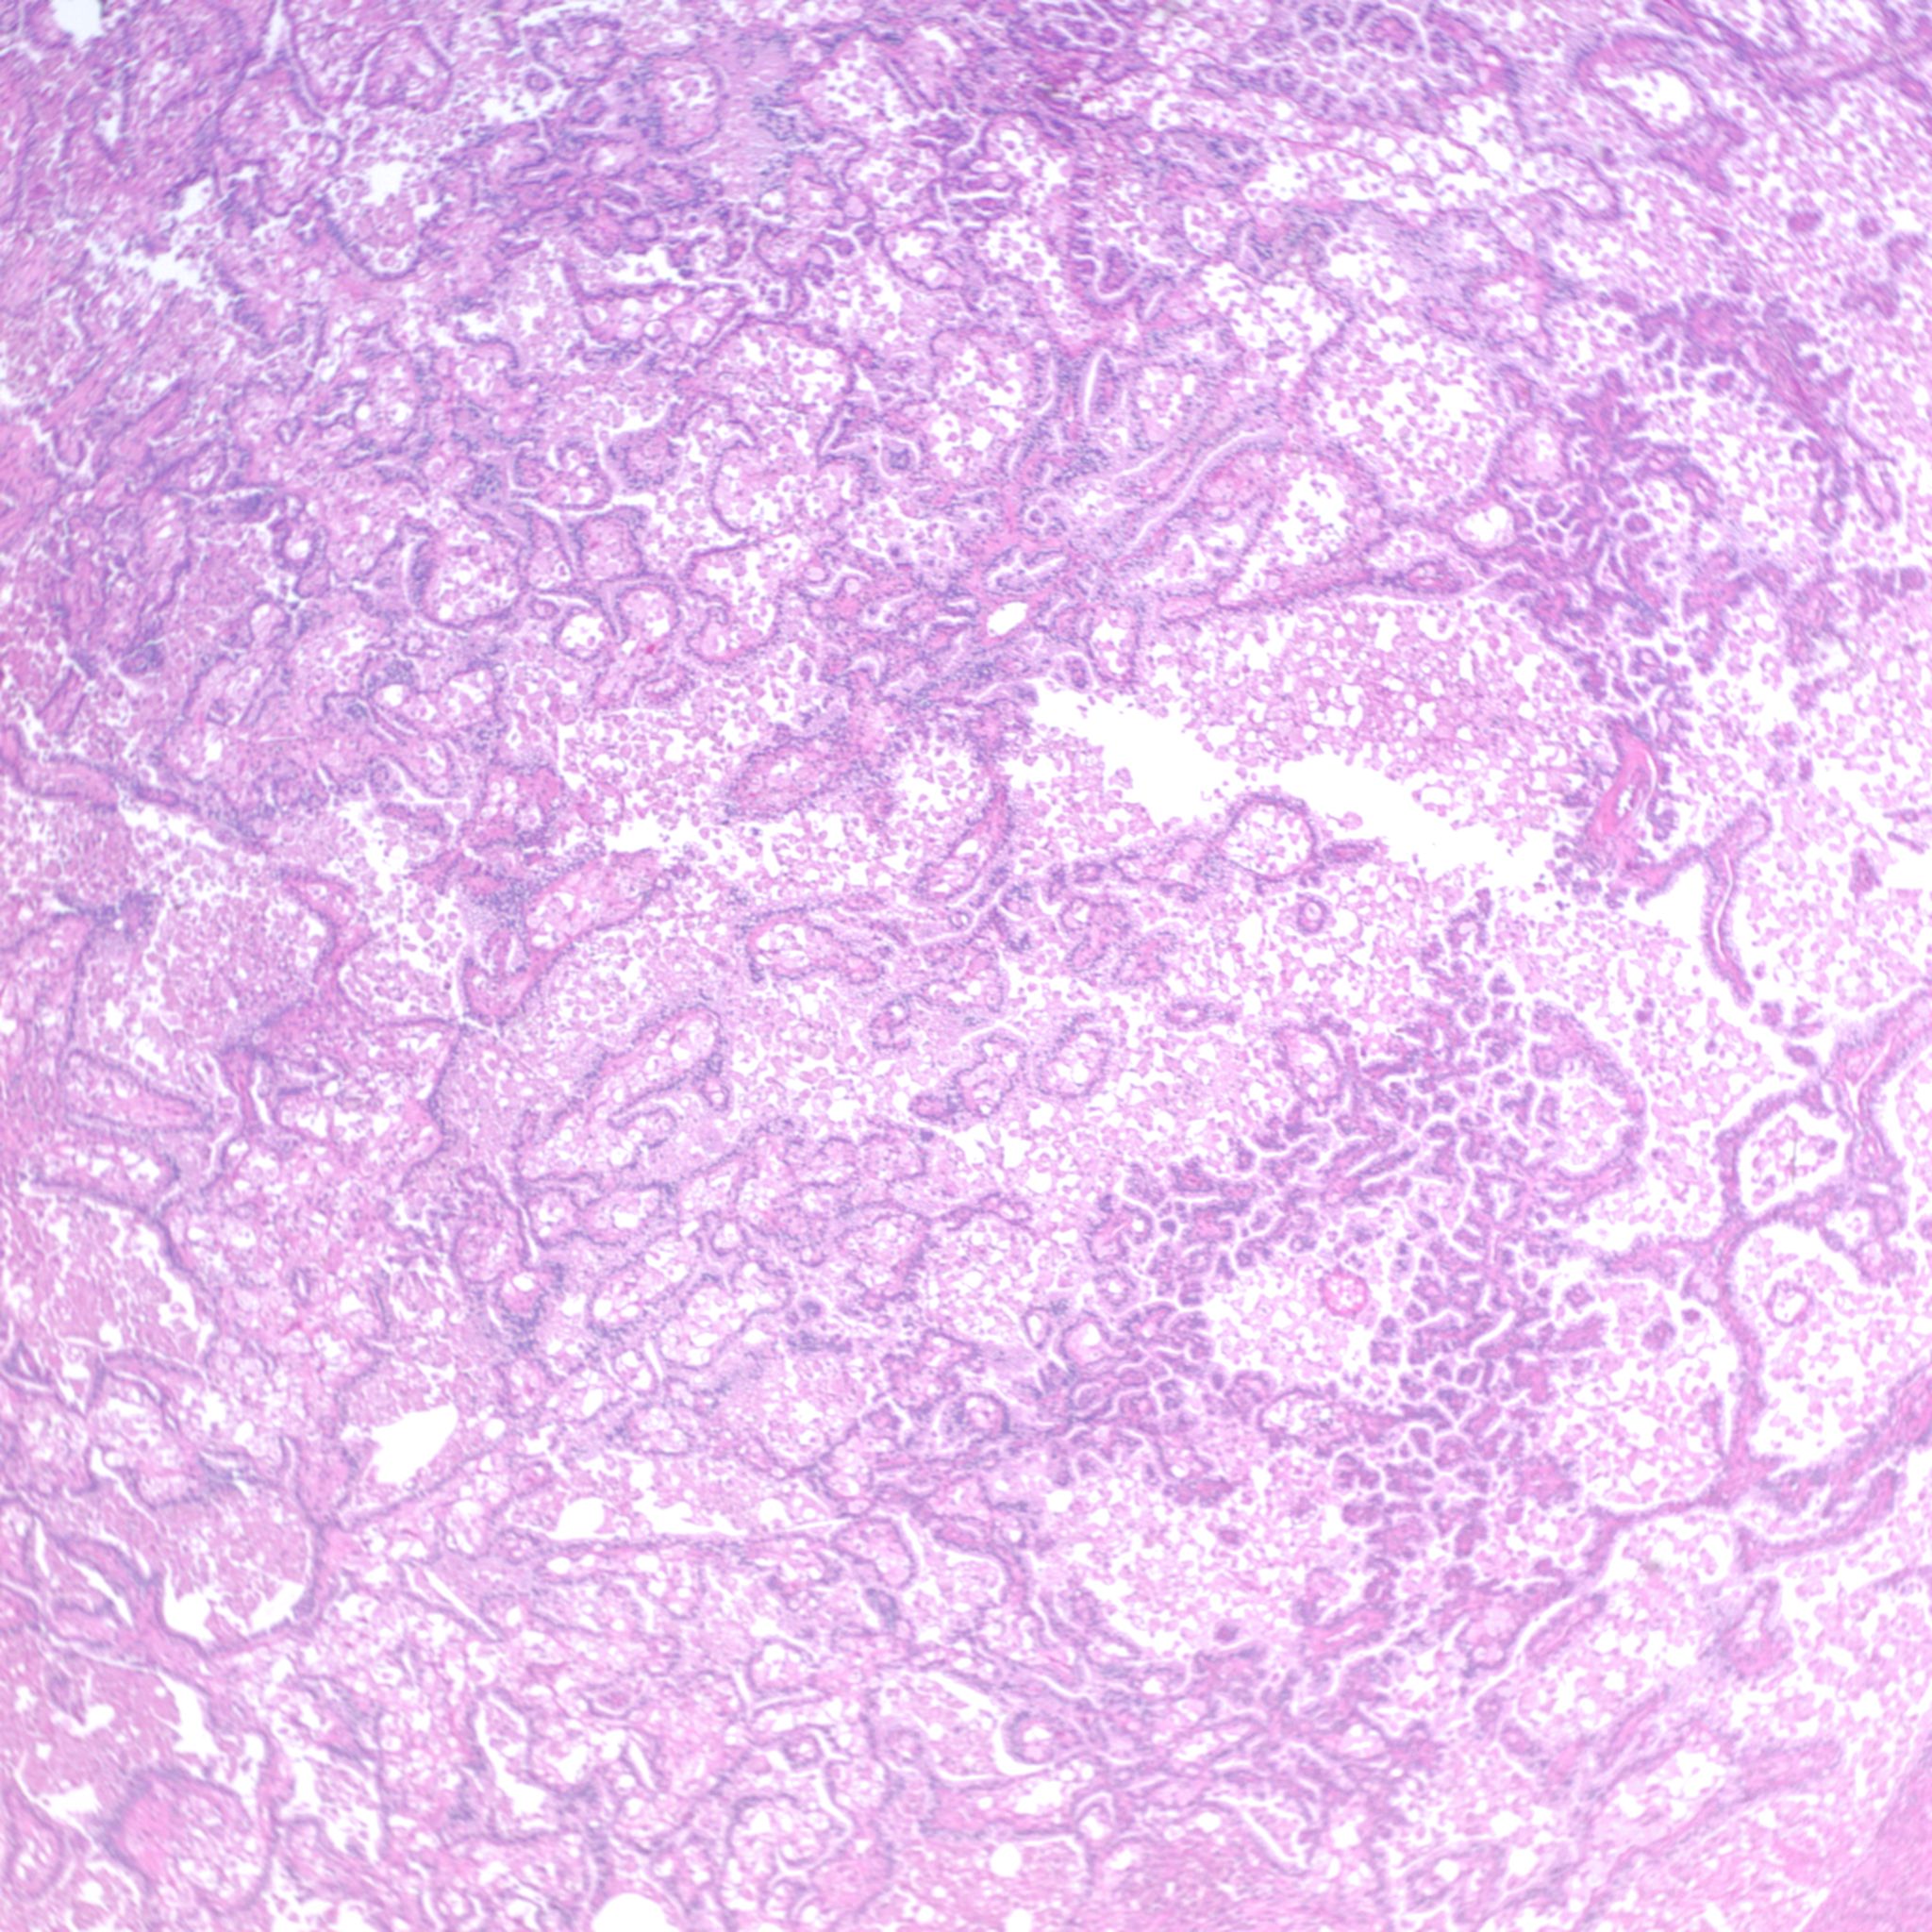

Case ID: 1225

Consensus grade: Papillary RCC (Type 1)

Case description (by case creator):

Papillary renal cell carcinoma, type 1, Fuhrman nuclear grade 2